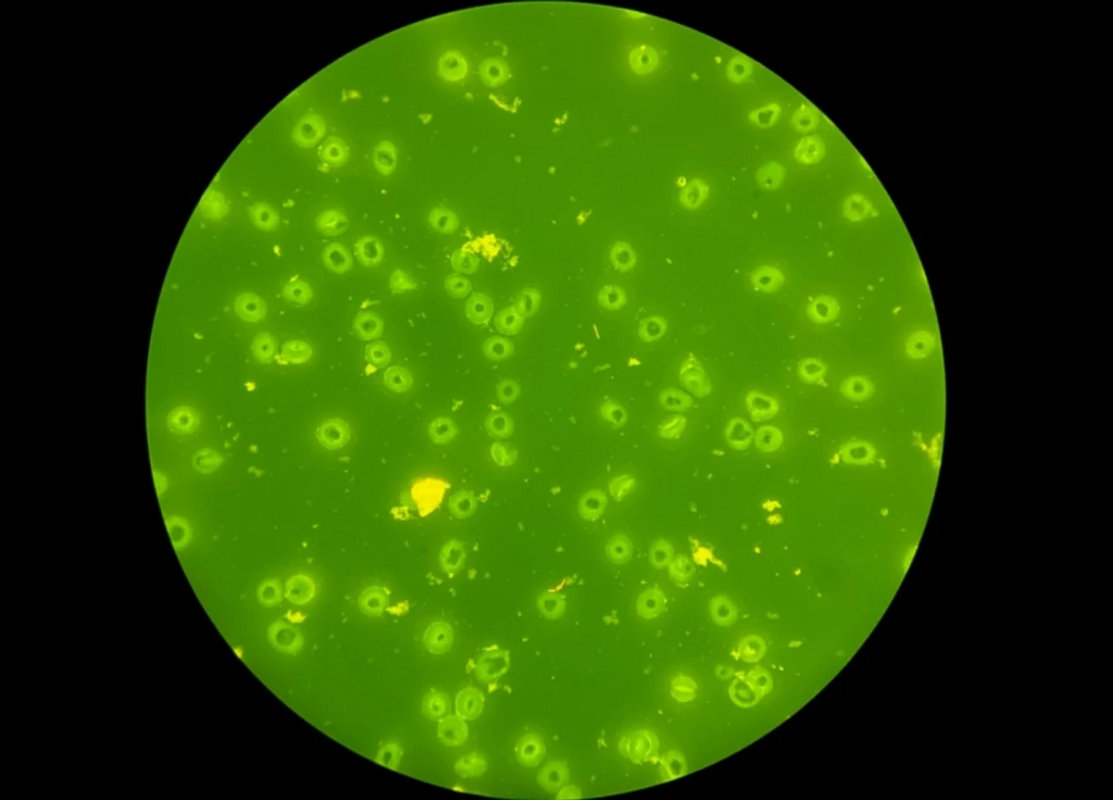

В соответствии с протоколом был проведен анализ мазков этой противоречивой культуры. Неокрашенный мазок, присланный лабораторией неотложной помощи, не был окрашен AO и не был просмотрен в соответствии с протоколом. Вместо этого, как упоминалось выше, было проведено окрашивание по Граму нового неокрашенного мазка, и он был признан NOS. При просмотре этого мазка, окрашенного АО были обнаружены длинные тонкие флуоресцирующие палочки с сужающимися концами (илл. 1).

Иллюстрация 1. Окраска акридиновым оранжевым.

Мазок, который был отправлен после второго положительного сигнала, но не был окрашен и прочитан, также был окрашен AO, и в нем были видны длинные тонкие флуоресцирующие палочки с коническими концами (илл. 2).

Акридиновый оранжевый (АО) - это флуорохроматический краситель, который связывается с нуклеиновыми кислотами микроорганизмов и клеток человека. РНК и одноцепочечная ДНК окрашиваются в оранжевый цвет, а двуцепочечная ДНК, содержащаяся в клетках человека, за исключением эритроцитов, окрашивается в желтый или желто-зеленый цвет при визуализации под ультрафиолетовым светом. Таким образом, бактерии и грибы окрашиваются в ярко-оранжевый цвет, а эпителиальные клетки, лейкоциты и фоновые фрагменты - в бледно-зеленый или желтый. Среди распространенных применений AO - рутинный скрининг обычно стерильных жидкостей организма и исключение грамположительных микроорганизмов на фоне преципитата, окрашенного кристаллическим фиолетовым. Важно отметить, что, несмотря на невозможность дифференцировать реальный микроорганизм, он помогает обнаружить Mycoplasma и Ureaplasma.